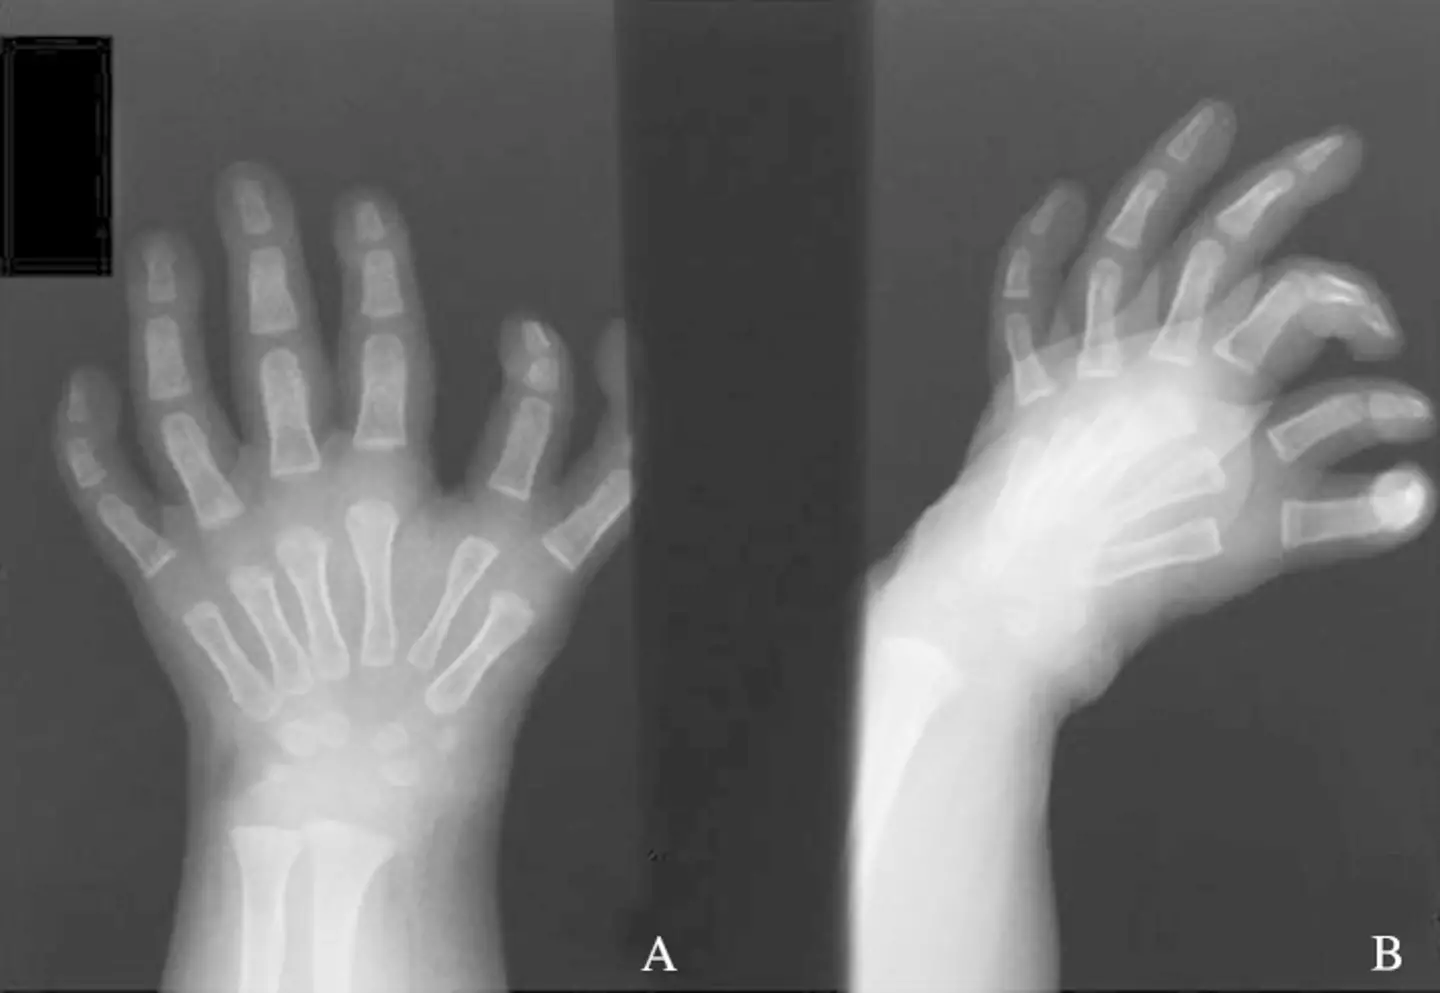

In one case documented by the US National Library of Medicine, a two-month-old girl was brought to the doctor for the reason of polydactyly - extra digits - and had some of the fingers amputated.

As you can see from the pictures, she had several surgeries which resulted in her having the ordinary number of fingers on her hand.

In this instance, they noted: “In the presented case of type II ulnar dimelia an anatomical correction of the hand was possible.

“The result of surgical treatment in both functional and cosmetic aspects was, in authors' opinion, good.”